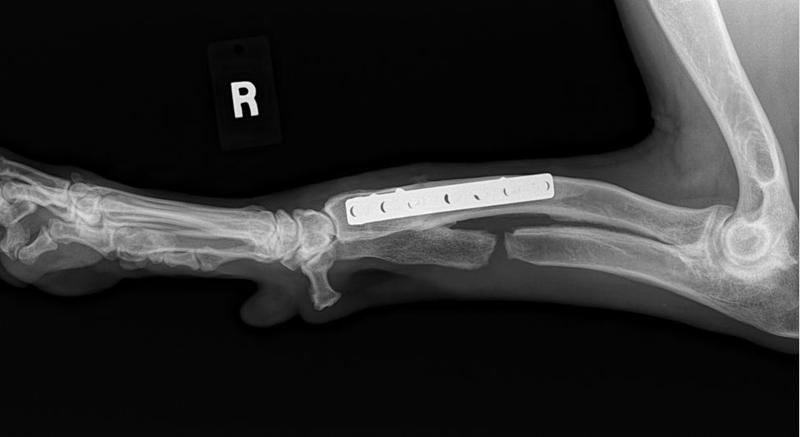

Her radius curvus syndrome was addressed, a bloat survivor and nothing ever held her back!